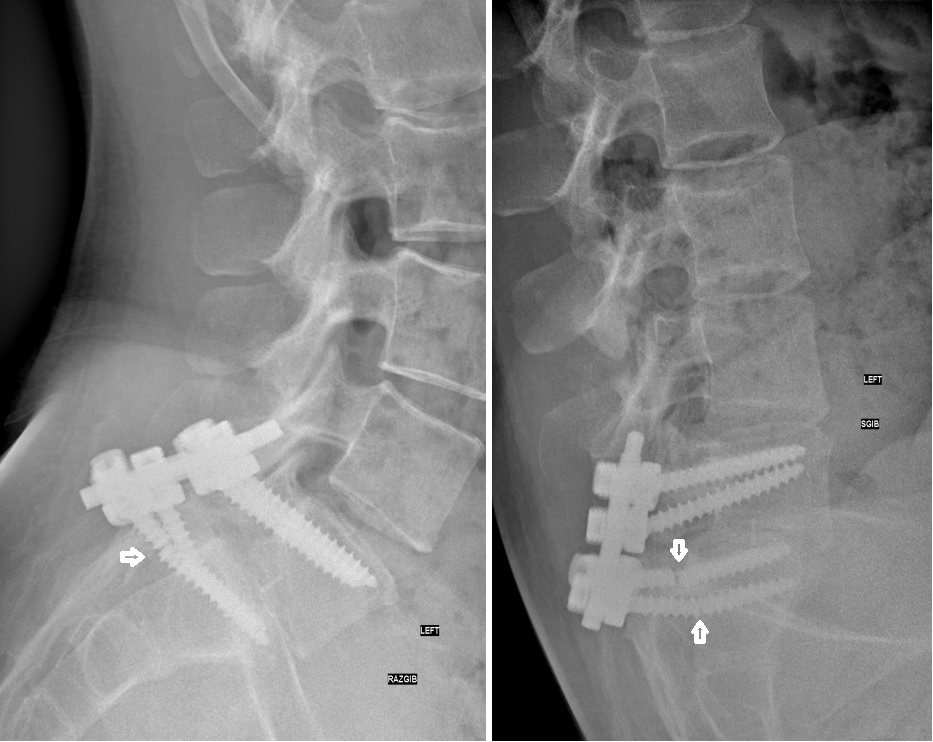

Это снимок не данного пациента, но так же с неудачей- перелом винтов.